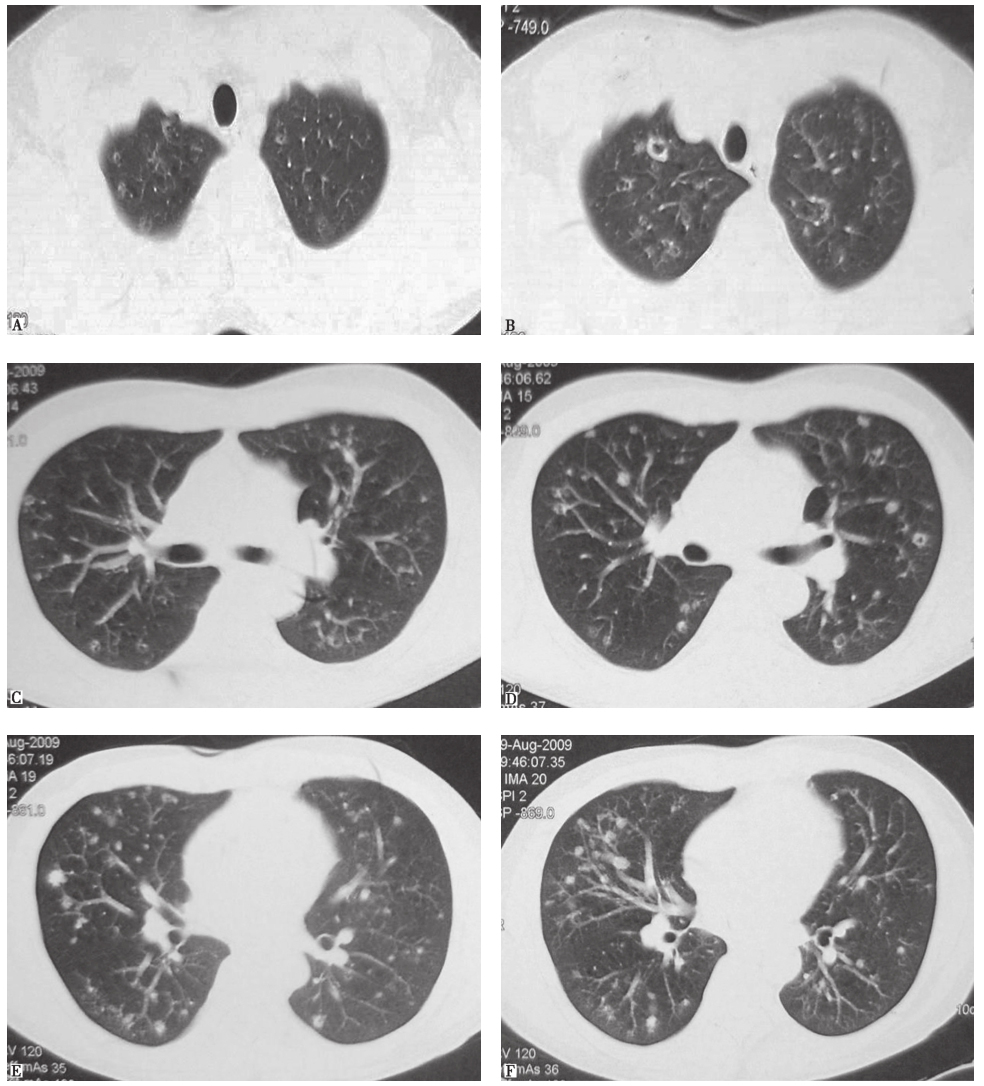

胸部CT可见双肺多发小叶中心型小结节影,部分为空泡影,病灶以中上肺分布为主,肺底病变不明显,散在分布(图1)。

图1入院前3周胸部CT表现

4.胸部CT可见双肺沿支气管走行分布为主的多发结节及空洞,以中上肺分布为主,肺底和膈肋角肺野病灶稀少。

一些非感染性疾病的胸部影像学表现也可见肺内多发结节、空洞影:①恶性肿瘤肺内转移,包括肺外肿瘤或原发肺肿瘤肺内转移,一般病灶的时相一致,转移结节在分布上呈现随机性,无明显中上肺部分布倾向;②职业肺病:多种金属粉尘暴露所致肺病的胸部影像学表现可见肺内随机分布或沿气道分布的结节,但一般没有空洞影。本例患者无类似暴露史,故不考虑职业肺病可能;③肺朗格汉斯细胞组织细胞增生症(pulmonary Langerhans cell histiocytosis,PLCH):以过量活化朗格汉斯细胞(Langerhans cell,LC)在器官内增殖、浸润为特征,病理特征为特异的组织细胞(朗格汉斯细胞)增殖,伴嗜酸细胞浸润。肺内病变可以为边界不清的结节影、空洞影、囊泡影。病变早期以小叶中心性结节为主,直径在1~5mm;病程后期表现为弥漫分布的囊泡影,囊泡壁厚薄及大小不一、形态不规则,囊泡直径通常为1cm,最大可至3cm;胸膜下肺大疱也不少见。病灶以双中上肺分布为著,自上而下发展,双侧肋膈角一般不受累。疾病晚期,病灶可以累及全肺。对于本病例,结合影像学表现,需要高度怀疑PLCH的可能。